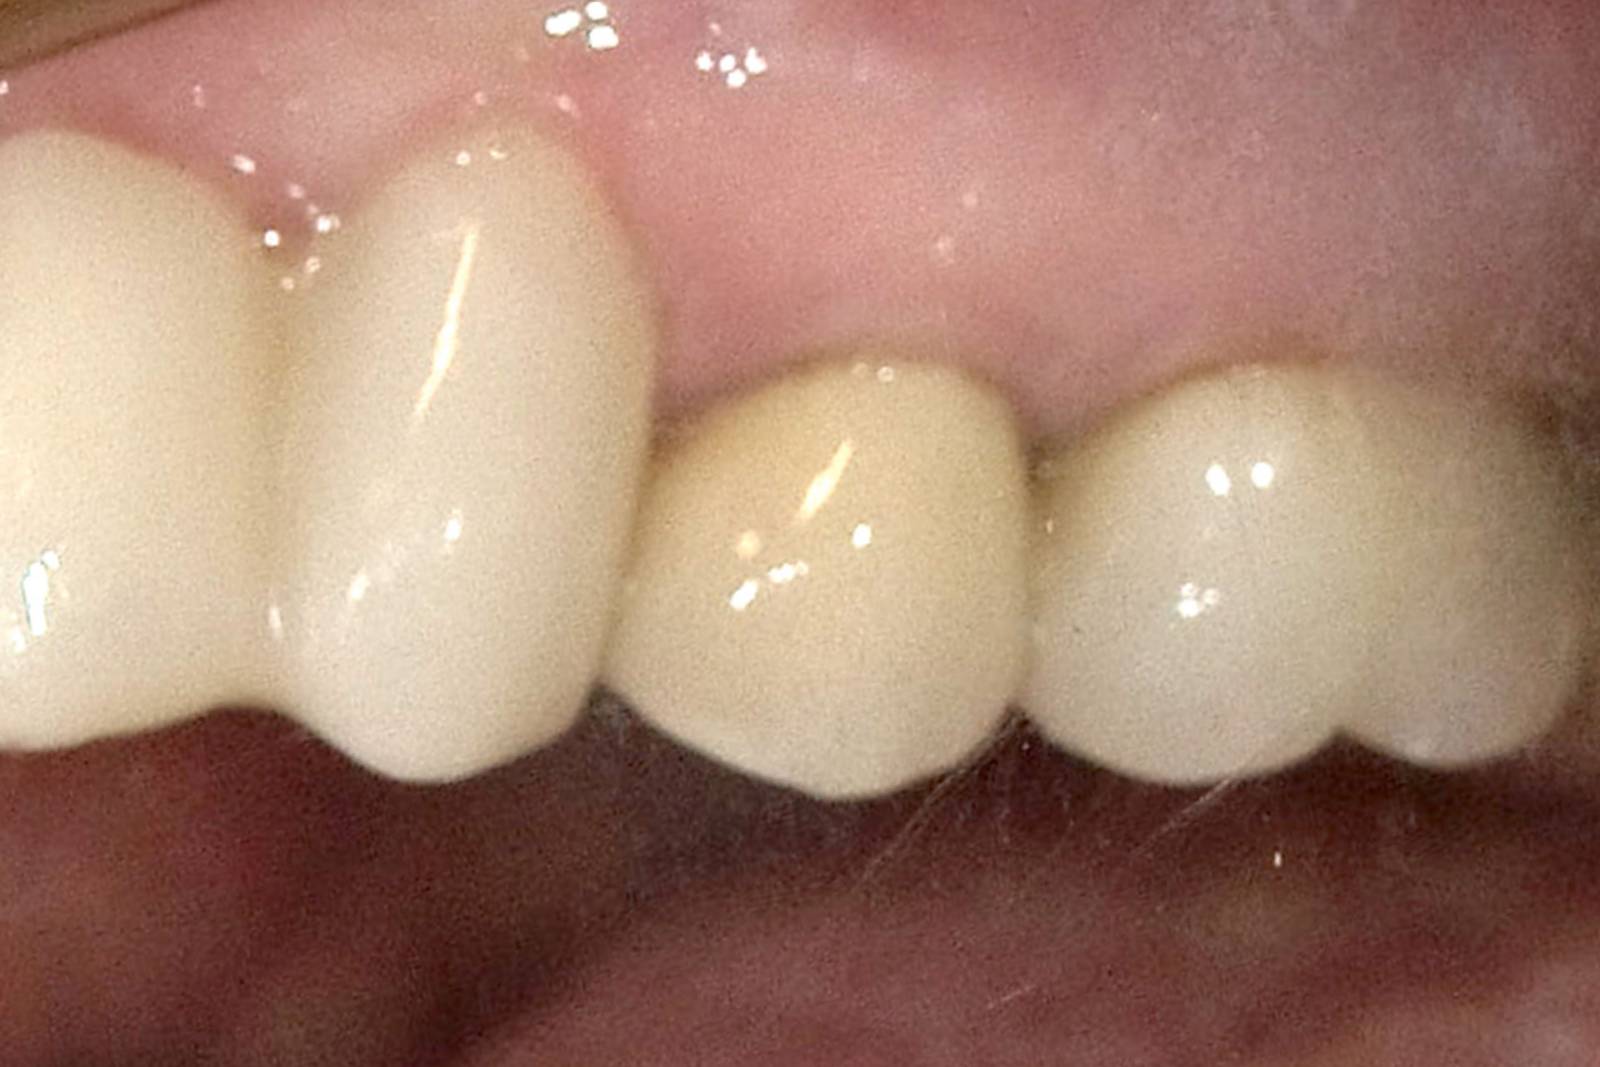

Before: A large carious mesial lesion on tooth 15. The tooth showed asymptomatic apical periodontitis and a significant loss of tooth structure.

After: Chairside-fabricated restoration made of CEREC MTL Zirconia designed using the Biogeneric individual function in the CEREC Software.